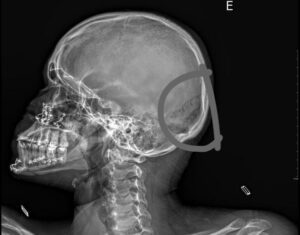

Segundo a vítima, o relacionamento começou em 2019 e, logo nos primeiros meses, teriam surgido episódios de violência. Em 2021, ela registrou dois boletins de ocorrência, de episódios ocorridos no Bairro Centro, no município tijucano, incluindo um que resultou em atendimento hospitalar e laudo médico apontando lesão intracraniana. Apesar disso, a mulher não solicitou medidas protetivas na época, alegando que alternava períodos de separação e reconciliação.

Imagem: L.W.R.M